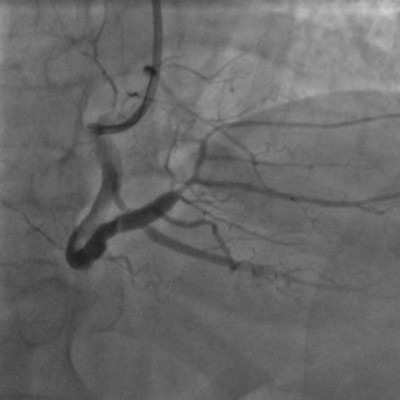

右圖:置放支架後恢復通暢的血管主幹。

急救過程,由王惠生醫師將血栓抽乾淨,能清楚看見右冠狀動脈原發病灶,即血管壁上的斑塊,再由劉維新醫師精準置放支架,完成血管的暢通。萬先生於術後三日移除葉克膜、五日後脫離呼吸器,並於術後一週自加護病房轉至普通病房,復健半個月後即出院。